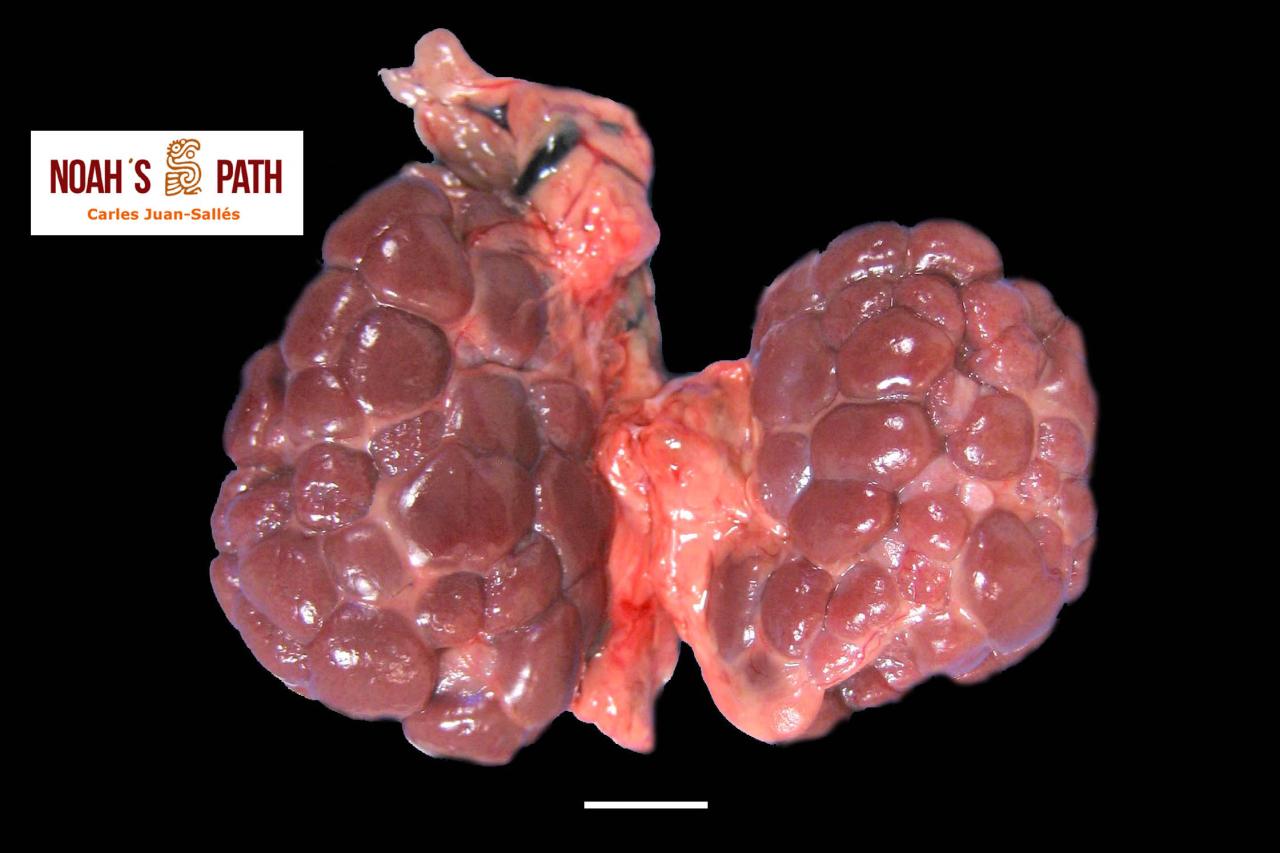

El examen post mortem ofrece una oportunidad única de acceso a todos los tejidos del paciente para diagnóstico de las causas de enfermedad y muerte, y por lo tanto es esencial para medicina preventiva y curativa en grupos de animales, seguimiento de casos, estudios sobre enfermedades, control de zoonosis, medicina de la conservación, y patología forense. En Noah's Path pensamos que un examen post mortem de este tipo de fauna debería ser realizado siempre que sea posible por patólogas/os especializadas/os con el fin de obtener el máximo de información y obtener las muestras más adecuadas.